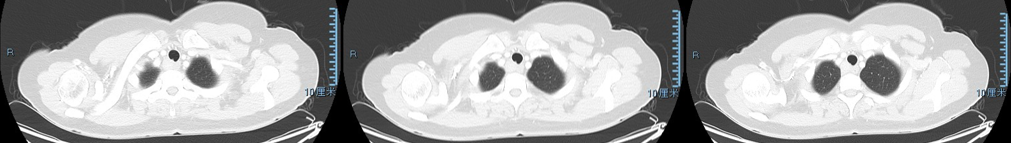

图1 颈胸部CT(2021-10-18):“1组淋巴结”增大(箭头所指)